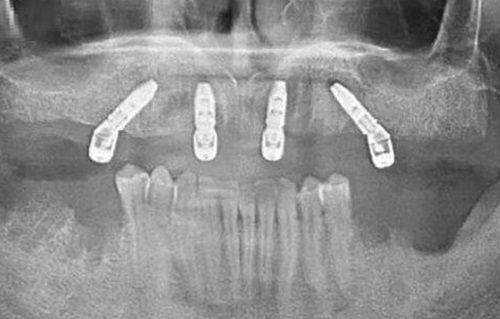

南通摩尔口腔医院种植牙多少钱?这是南通本地缺牙患者问得更多的问题。作为扎根南通多年的老牌口腔机构,南通摩尔口腔医院种植牙价格其实特别接地气——单颗从4980元起,全口从88000元起,覆盖“高性价比入门”到“高端定制”,不管你是缺一颗牙想省钱,还是全口无牙想求稳,都能找到匹配方案。今天就把南通摩尔口腔医院的种植牙价格、技术、医生情况一次性说透,帮你避开“种牙坑”。

5、All-on-4全口种植:88000元起/副(全口无牙?上下各4颗,当天种当天吃)

6、All-on-6全口种植:118000元起/副(骨量差?多2颗更稳,适合老年人)

南通摩尔口腔医院种植牙多少钱?总结下来,单颗跨度4980-15800元,全口88000-118000元。核心差异在“种植体+牙冠+附加技术”——韩国品牌比瑞士便宜近一半,全瓷冠比烤瓷冠贵1000-3000,骨增量要加3000-5000。但价格透明,术前给详细报价单,无隐形消费。不过以上是参考价,具体得看你口腔情况:有没有牙周病、骨量够不够,更好先做免费CT(南通摩尔能预约!)。